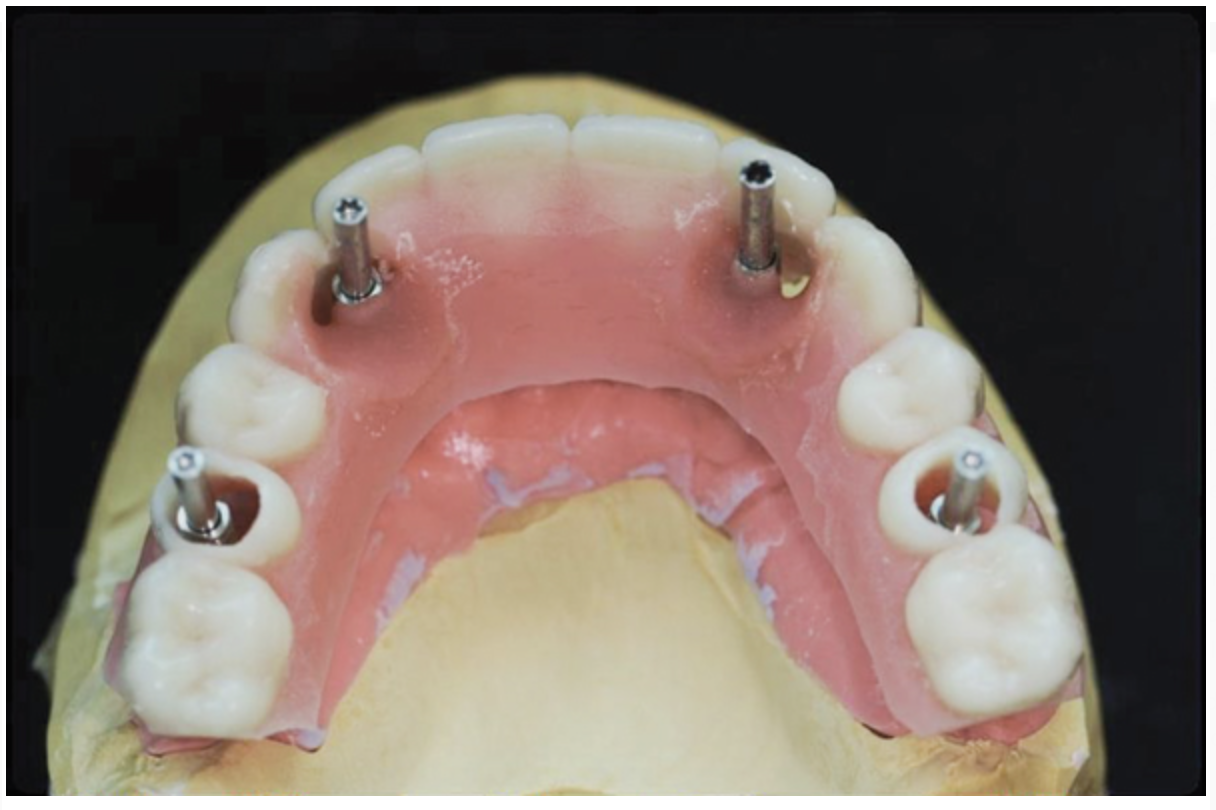

To start, a surgical impression is performed. Open-tray impression copings are secured to the restorative abutments, and a denture-strengthening bar is attached to the copings using a low-expansion pattern resin. The “salt and pepper” technique is used for precise control of the material, thereby avoiding contact with the surgery site and more effectively controlling working time. A plastic impression tray is modified in the occlusal areas where the impression copings will emerge and is tried-in to verify that there are no interferences. Polyvinylsiloxane impression putty is mixed and adapted over the impression copings and denture-strengthening bar. Impression material is also placed in the tray prior to seating. The impression coping screws are exposed and disengaged, allowing the impression to be easily removed. Rigid stabilization of the copings in the impression is verified (Figure 10 through Figure 12). The surgical index is performed using the same provisional prosthesis guide used during the surgery. Only the two anterior implants are indexed. The provisional prosthesis guide is seated to verify the absence of interferences with the two anterior temporary cylinders, and cold-cure acrylic material is applied through the access windows using a “salt and pepper” technique (Figure 13). The prosthesis is held in place with light pressure on the prosthesis guide over the palate or the posterior lingual mandibular ridge until the resin is cured. The VDO is verified after guiding the patient into occlusion with a bite registration recorded in the lab. Esthetic and functional parameters are verified, and the indexed prosthesis is removed with the attached temporary cylinders, and it is then disinfected in cold sterile solution.

The dental technician fabricates a master cast with a soft-tissue model while the indexing and VDO procedures are performed. A silicone material is added around the implant analogues in the surgical impression before model pouring with zero expansion stone (Figure 14 and Figure 15). The soft-tissue model is removed to verify a precise fit of the temporary titanium cylinders indexed in the mouth to the master cast. The indexed provisional prosthesis is modified to allow passive attachment of the posterior temporary cylinders to the prosthesis using heat-cured acrylic processed under pressure. The technician then removes the cold-cure acrylic that was used to index the two anterior temporary components and re-secures them with fresh heat-cured acrylic under pressure (Figure 16). The intaglio surface of the provisional prosthesis is finished with cold-cure acrylic on the master cast and polished to ensure a convex surface with sufficient space to allow for tissue swelling and access for hygiene.

Fig 10. Surgical impression—Open-tray impression copings are secured and splinted with a denture-strengthening bar using low-expansion pattern resin.

Figure 10

Fig 11. Surgical impression—Modified plastic impression tray seated to verify that there are no interferences with the copings or the bar.

Figure 11

Fig 12. Surgical impression—After impression putty is adapted around the impression copings and bar, the tray is filled with impression material and seated, the copings are exposed, and the retention screws are disengaged to allow the impression to be easily pulled.

Figure 12

Fig 13. Surgical indexing of the two anterior implants—After verifying that the modified provisional prosthesis fully seats without interferences with the temporary cylinders attached to the anterior two implants, cold-cure acrylic material is applied using a “salt and pepper” technique.

Figure 13